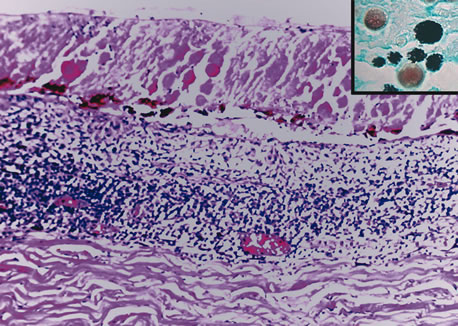

Inflammatory conditions may also lead to iris nodules. Patients suffering from fungal endophthalmitis may demonstrate an irregular yellow-white mass on the iris. Histologically, these appear as necrotizing granulomas containing mycotic agents (Fig. 2). In juvenile xanthogranuloma, a yellowish-gray iris lesion may be associated with spontaneous hyphema, and histopathologically the nodules demonstrate diffuse histiocytic infiltrate (Fig. 3). Multinucleated giant cells displaying peripheral foamy cytoplasm are also noted; these cells are known as Touton giant cells.29 The giant cells and the histiocytes contain lipid that can be demonstrated by oil red O stain.

Fig. 2. Coccidioidomycosis. Iris stroma shows necrotizing granuloma containing mycotic organisms. The organisms show features of Coccidioides immitis. (Hemotoxylin-eosin ×60.)